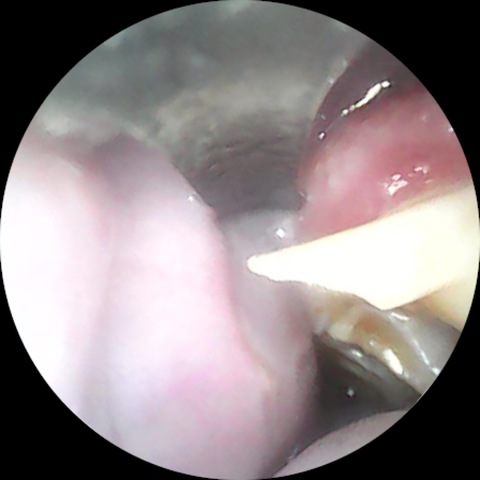

臼歯は、噛み合わせが悪いせいで摩耗せずに過長すると、舌や頬粘膜に刺さってかなりエグることがあります

(右下顎臼歯が舌に刺さって傷つけていた、カット後の様子)

(頬粘膜側に伸びていた右上顎臼歯の棘をカットしたビフォーアフター)